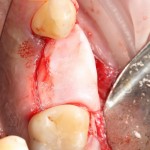

В этом случае остеопластика делается отдельной процедурой. Ее принципы точно те же, но уже без импланта. Например:

Имплантировать в таких условиях — заведомо обрекать себя на хреновый, с точки зрения эстетики и функциональности, результат. Поэтому первым этапом проводим остеопластику. Объем небольшой, использовать в таких объемах костный блок не очень рационально. Воспользуемся аутокостной стружкой и мембраной.

Сначала фиксируется BioGide. Это легко:

Затем укладывается и конфигурируется аутокостная стружка: